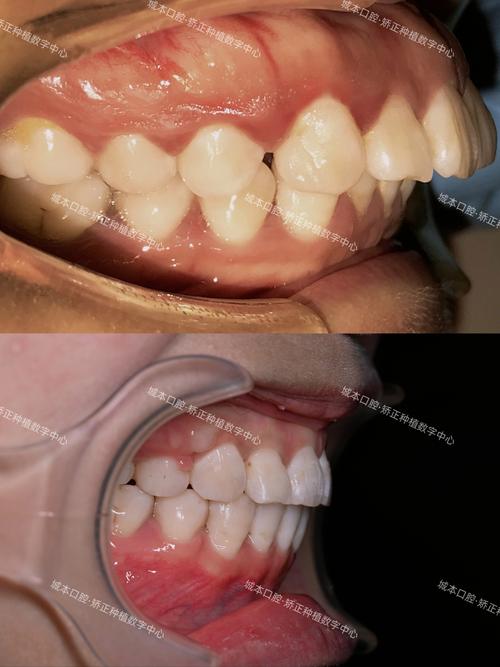

侧切牙内凹是口腔正畸中常见的牙齿畸形类型,主要表现为上颌侧切牙牙冠向舌侧倾斜,导致牙颈部唇侧膨隆、牙冠唇面看起来“凹陷”,常伴随牙齿扭转、牙间隙或咬合异常等问题,这种畸形不仅影响微笑美观,还可能因牙齿清洁困难增加龋病、牙周病风险,严重时会导致咬合功能紊乱,因此需通过正畸治疗进行干预。

从危害来看,美观上,内凹的侧切牙会破坏微笑弧线的对称性,尤其在前牙区显露明显时,影响个人形象;功能上,牙齿倾斜可能导致咬合时受力不均,长期易引发颞下颌关节紊乱;健康上,舌侧倾斜的牙齿邻接关系异常,易嵌塞食物,加之清洁难度增加,易导致牙龈炎、牙周炎,甚至牙槽骨吸收。

正畸治疗通过施加持续、轻柔的生物力,利用牙齿与牙槽骨之间的改建能力(即“骨改建”),移动牙齿至正常位置,针对侧切牙内凹,治疗核心目标包括:纠正牙齿舌侧倾斜,使牙长轴与牙弓中线平行;关闭可能存在的牙间隙;调整咬合关系,确保前牙覆颌覆盖正常、后牙尖窝交错稳定;最终实现功能与美观的统一。